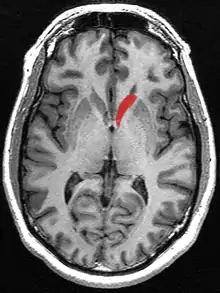

Caudate nucleus

![]() Caudate nucleus (in red) shown within the brain | |

The caudate nucleus is one of the structures that make up the corpus striatum, which is a component of the basal ganglia in the human brain.[1] While the caudate nucleus has long been associated with motor processes due to its role in Parkinson's disease,[2][3] it plays important roles in various other nonmotor functions as well, including procedural learning,[4] associative learning[5] and inhibitory control of action,[6] among other functions. The caudate is also one of the brain structures which compose the reward system and functions as part of the cortico–basal ganglia–thalamic loop.[1]

The caudate nuclei are located near the center of the brain, sitting astride the thalamus. There is a caudate nucleus within each hemisphere of the brain. Individually, they resemble a C-shape structure with a wider "head" (caput in Latin) at the front, tapering to a "body" (corpus) and a "tail" (cauda). Sometimes a part of the caudate nucleus is referred to as the "knee" (genu).[7] The caudate head receives its blood supply from the lenticulostriate artery while the tail of the caudate receives its blood supply from the anterior choroidal artery.[8]